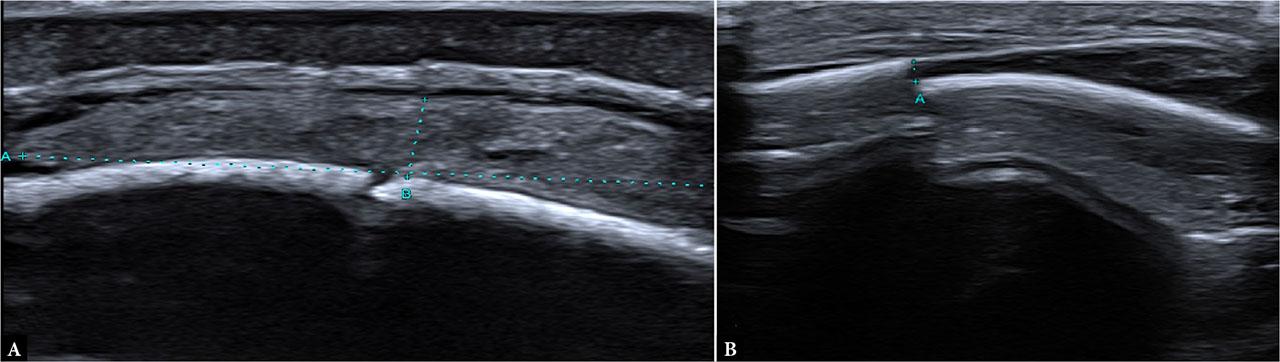

All patients were first clinically evaluated by a pediatric surgery resident or specialist in the emergency department. Based on surgical assessment, patients were referred to the radiology department, where ultrasound examinations were performed in a dedicated ultrasound room using a CANON Aplio i700 ultrasound machine, equipped with a high-frequency linear transducer (11–18 MHz). Children were positioned supine or, in cases of occipital trauma, in a prone or sitting position, accompanied by a caregiver, with gentle immobilization applied when necessary to minimize motion artifacts. The area of impact, hematoma, or maximal tenderness was systematically scanned in both longitudinal and transverse planes, with additional sweeps of adjacent and contralateral regions for comparison. In the absence of clear clinical signs of impact area, or problems with indicating the expected site of injury (non-verbal children), a broader portion of the skull was routinely examined. Particular attention was paid to differentiating fracture lines from normal cranial sutures at the affected site by tracing sutures to a fontanelle where possible or by comparing with symmetric contralateral structures. Major cranial sutures were assessed only at the affected site and adjacent collateral locations to distinguish normal suture lines from potential diastasis. ( Fig. 1, Fig. 2, Fig. 3, Fig. 4) No cases of sutural diastasis were identified in the cohort. All scans were performed by 15 radiology department physicians, either trained pediatric radiology residents or board-certified specialists. Interobserver variability was not formally evaluated.

Examples of skull fracture fissures observed on ultrasound in (A) a 2-month-old boy and (B) a 1-month-old girl. A. Fracture fissure of the parietal bone with an associated subperiosteal hematoma (calipers). B. Fracture fissure of the parietal bone with a 1-mm cortical invagination (calipers)